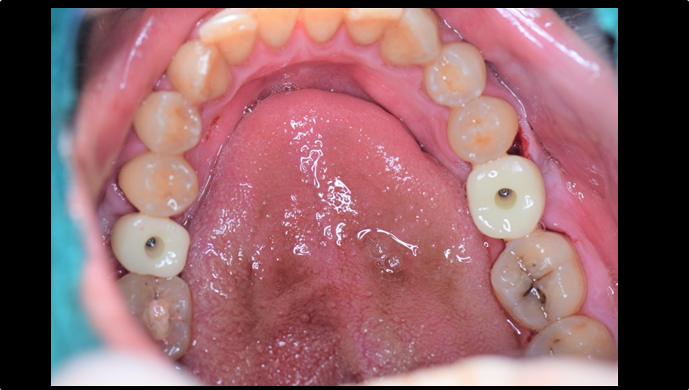

Clinical case: EImmediate implant placement & loading of #35 extraction socket with defect

- Courtesy of Dr. Kwang Bum Park, Korea -

Dr. Kwang Bum Park, immediate loading, digital guided surgery, digital ONE-DAY implant, maxillary anterior, #21, guided surgery, immediate loading, AnyRidge, R2GATE, Mega ISQ, MEG Torq, R2GATE Full Surgical Kit

implant system, R2GATE Guide, R2GATE surgical kit (AnyRidge), Mega ISQ, Mega-Oss

“ One implant /One tooth/ One hour step-by-step

+ associated connective graft ”